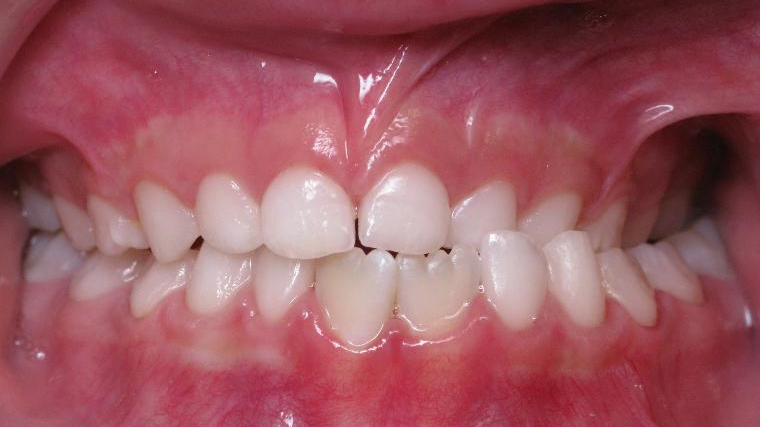

9. inversé gauche 6 ans

inversion des dents posterieur cote gauche